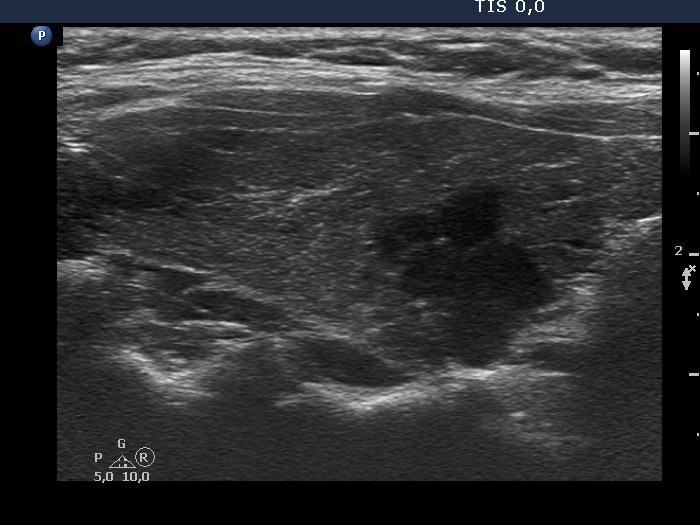

Ultrasonography. The thyroid was minimally hypoechogenic and had several discrete more hypoechogenic areas, including a cluster composed of multiple discrete lesions in the dorsal part of the left lobe. These lesions had irregular, partly lobulated, partly spiculated margins. However, the entire pattern corresponded to Hashimoto's thyroiditis.

Regarding the nodule borders the lesions presented partly lobulated, partly spiculated margins. However, these should not be held as pathological nodules, the discrete lesions are presentations of more active foci of Hashimoto's thyroiditis, which is an infiltrative process and therefore frequently has infiltrative, irregular margins.